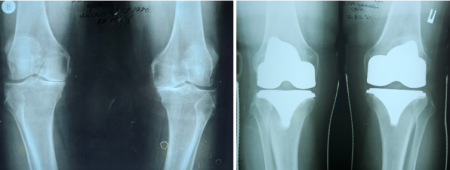

Медики відділення ортопедії та травматооогії Закарпатської обласної клінічної лікарні імені Андрія Новака виконали ендопротезування обох колінних суглобів військовослужбовцю. Оперативне втручання провели за державною програмою.

Юрію – 55 років, він служить сапером в одному з підрозділів з початку повномасштабного вторгнення РФ. За словами захисника, через надмірне навантаження під час виконання бойових завдань, з часом почали турбувати інтенсивні болі в обох колінних суглобах, з’явилася їх деформація та різке обмеження рухів.

До Закарпатської обласної клінічної лікарні пацієнта госпіталізували з діагонозом «Двобічний гонартроз IV ступеня з варусною деформацією обох колінних суглобів, стійким больовим синдромоммом та згинально- розгинальною контрактурою середнього ступеню».

«Хворому провели тотальне цементне ендопротезування лівого і правого колінних суглобів. Післяопераційні періоди проходили без ускладнень. У задовільному стані пацієнта виписали в реабілітаційне відділення ЗОКЛ ім. А.Новака, де він пройшов курс повноцінного відновно-реабілітаційного лікування», – розповів Іван Дорогій.